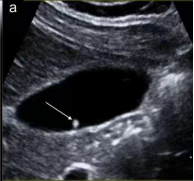

首选检查为超声检查,该检查无创、方便易行、廉价,对息肉的形态、血流有很好的判断,尤其对胆囊胆固醇沉积症、胆囊腺肌症等有独特的影像显示,是常规体检、随访的必备检查。

如超声检查探及血流信号,则肿瘤性息肉可能性大,不论息肉大小,应及时行胆囊切除术。